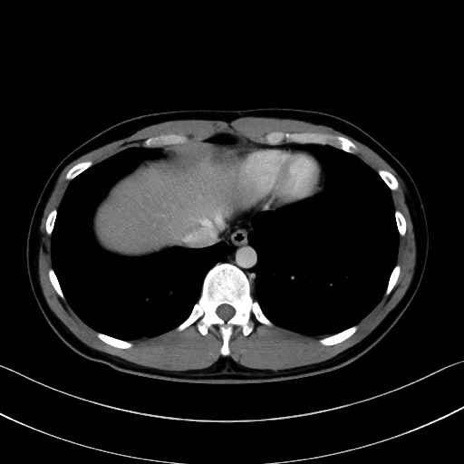

2. 腸腰筋群と骨盤底筋

大腰筋 (Psoas major)

腸骨筋 (Iliacus)

肛門挙筋 (Levator ani)